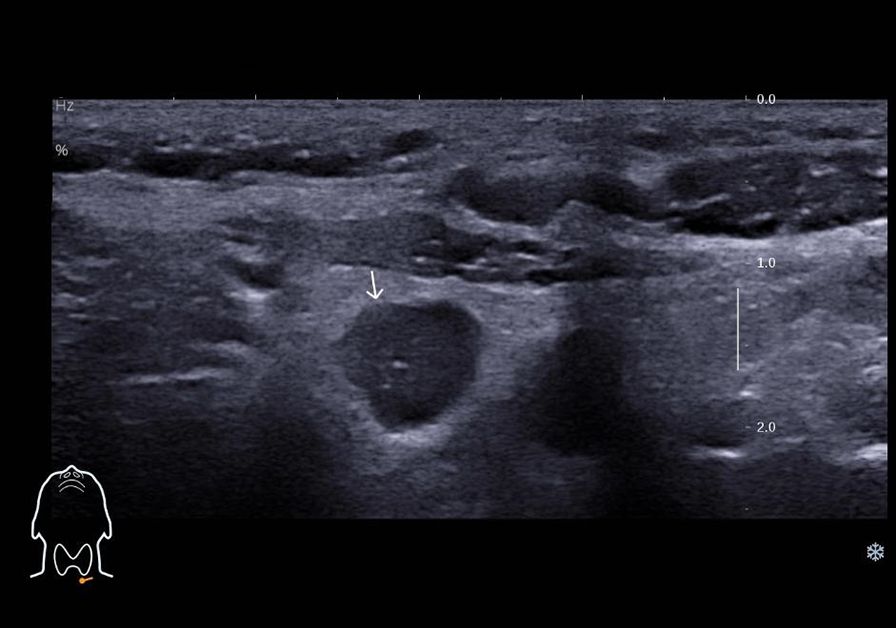

Figure 2

Ultrasound scan image showing cross-sectional view of neck tissues. A light arrow points to a circular area, possibly indicating an abnormality or structure of interest within the tissue layers. Measurements are marked on the right side. A small diagram of a head with throat is visible at the bottom left.

Figure 2. Ultrasound image depicting lymph node metastasis of medullary thyroid carcinoma in cervical region VI, demonstrating internal fine calcifications.